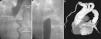

Angiography from the right radial (Figure 1A) and femoral (Figure 1B) arteries showed dilatation of the ascending aorta with maximum diameter of 47mm and aortic coarctation with total occlusion of the descending aorta after the origin of the left subclavian artery (Figure 1A). The gradient between the ascending and descending aorta was 40mmHg. There was an extensive collateral circulation via the intercostal and left internal mammary arteries. Since it was impossible to cross the aortic coarctation, the descending aorta was replaced by a tube graft (Figure 1C).